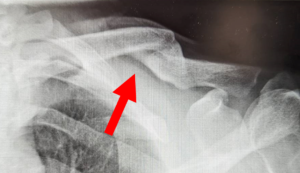

鎖骨は皮膚の直下にあり、表面に筋肉による被覆がほぼないため、骨折部が隆起し肉眼的に確認できることがしばしばあります。この肉眼的な膨隆がまるでテントが張られているようにみえるのでtentingといいます。

転位に伴う骨折部の肉眼変化(Tenting 赤矢印)